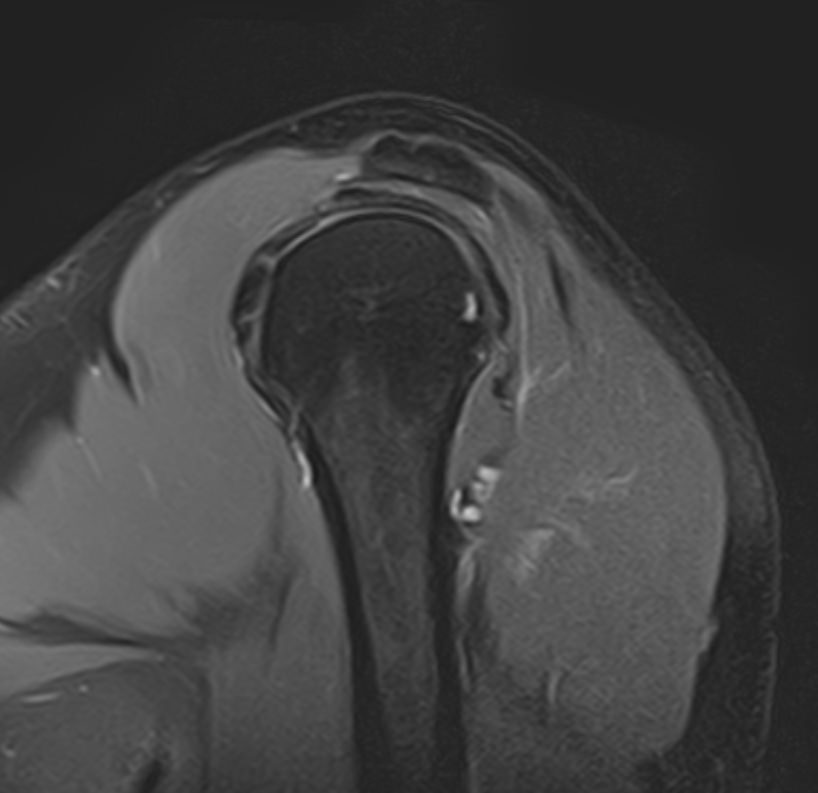

Плечевой сустав является наиболее подвижным сочленением, которое образовано лопаткой и головкой плечевой кости. У сустава нет мощных связок, он укрепляется мышцами плечевого пояса, окружающими его по типу корсета. Суставную капсулу образуют короткие связки, расположенные вокруг сустава. Благодаря такому строению сустав отличается высокой подвижностью, но при этом склонностью к вывихам. Полость сустава заполнена синовиальной жидкостью, питающей хрящи и служащей смазкой для них.

Метод МРТ позволяет оценить состояние всех анатомических областей плечевого сустава,  включая костную структуру, суставную капсулу, полость сустава с выстилающей его синовиальной оболочкой, связки, сухожилия, мышцы и окружающие мягкие ткани.

• Травмы плечевого сустава, различные переломы, при этом наиболее часто встречаются вывихи, что обусловлено анатомией сустава. Нередко травмы сустава с разрывом связок и сухожилий ведут в дальнейшем к развитию нестабильности плечевого сустава и могут стать причиной формирования привычных вывихов.